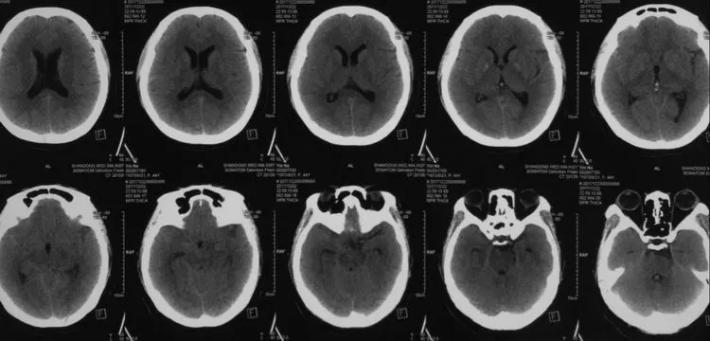

病史简介 患者中年女性,3天前突发头痛伴恶心、呕吐入院。无阳性病史。Hunt一Hess分级I级。CT示SAH,右鞍上池、侧裂根部出血较多。

蒙片看支架释放成形很好,远端由于脉前A的原因覆盖的较短,故而有少量逆向渗漏,但是蒙片看造影剂晚期滞留明显,与家属沟通后终止手术! 2周后切线位DsA造影可看到造影剂充盈BBA,造影剂与支架间形成一充盈平面,与术后DsA形态比较明显增大,而且M1有明显的痉挛。

这个BBA让人为难了,第一次选了Willis为了保脉前A支架远端覆盖较短,明明是逆向充盈有可能形成血栓偏偏是增大不愈,如何处理。 颈试验看前交通部分开放,后交通不开放;病人后续处理介入孤立不在考虑之列,安全的策略是术中搭桥十包裹夹闭术(备孤立),手术一要保留脉前A,二要通过搭桥保证McA区域血供,三要保证BBA完全包裹夹闭或孤立掉,病人不但需要治愈BBA挽救生命,更需要保功能有个健全人生,因为她还年轻!!!